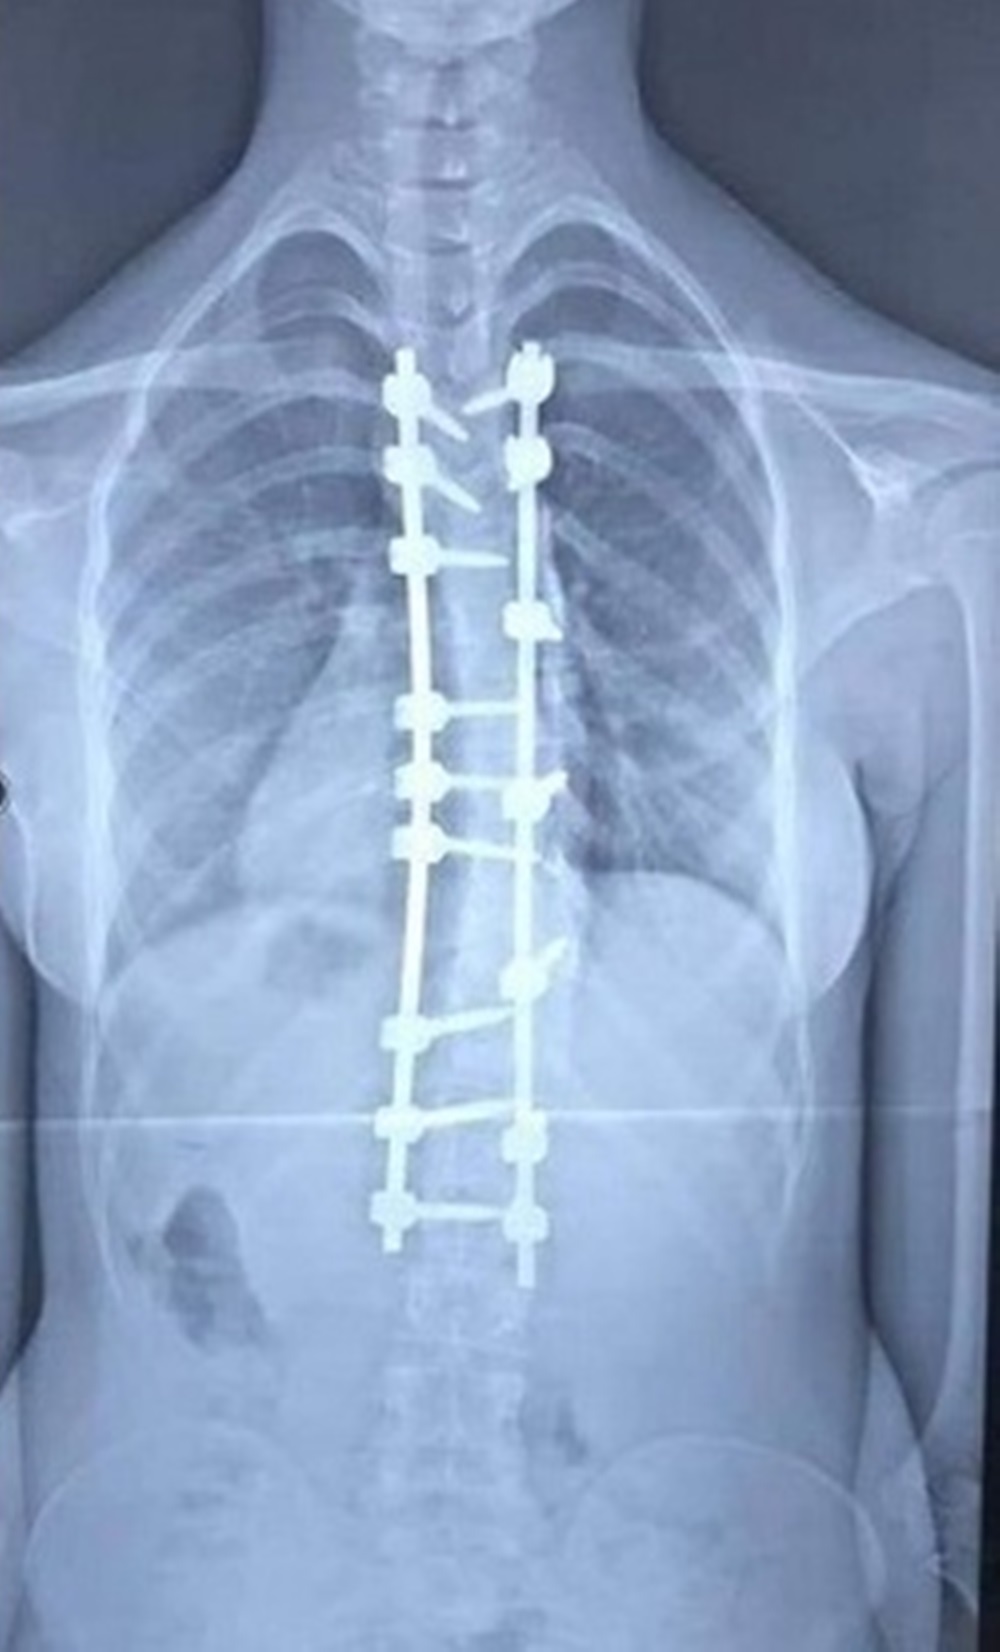

أعلن فريق طبي في مستشفى الكفيل التخصصي بكربلاء، نجاحه بعملية تعديل جنف العمود الفقري لمريضة ستينية.

وقال إختصاصي جراحة العمود الفقري بالمستشفى الطبيب اللبناني، دكتور عامر السبعلي، في حديث صحافي، إن فريقنا الطبي نجح بعملية تعديل جنف العمود الفقري (إنحراف وتحدب العمود الفقري) لمريضة تبلغ من العمر (63) عاما، مبيناً إن الجنف بنسبة (35%)، وإن المريضة تعاني من تضييق في مجرى الدودة يرافقه آلام حادة جعلتها غير قادرة على ممارسة حياتها بشكل طبيعي.

وأشار السبعلي إلى، إن العملية إستغرقت خمس ساعات، بمساعدة فريق طبي متميز وأطباء تخدير ماهرين، فضلاً عن وجود التقنيات الحديثة التي شجعتنا على إجراء العملية، مؤكداً إن العملية كانت ناجحة والمريضة أستعادت إستقامة ظهره عقبها وهي الآن تتمتع بصحة جيدة.